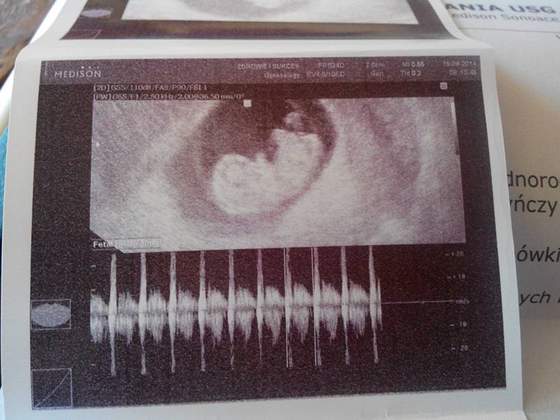

Nie jestem juz fasolka, ale małym człowieczkiem, mam mini nosek, nozki i ramionka. Mierze 22mm. Serducho bije jak dzwon! Byłem bardzo ruchliwy i pokazałem sie ze wszystkich stron, to białe nade mną to pępowina ;D